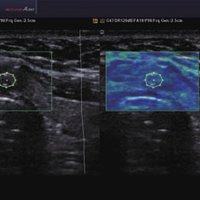

• ElastoScan™ ermöglicht eine genauere Visualisierung von Tumoren und erfasst und dokumentiert Gewebesteifheiten.

• Das Tissue Specific Imaging (TSI) optimiert die Qualität des Scans anhand der Beschaffenheit des Gewebes. Es kann aus 4 unterschiedlichen Bildmodi gewählt werden: Allgemein, Muskel, Fließend, Fett.